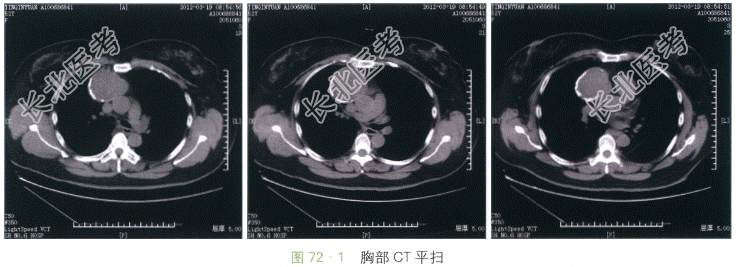

胸部CT(见图72-1~图72-2)提示右前纵隔软组织密度占位,边界清晰,边缘光滑并可见环形钙化,与周围大血管结构之间脂肪间隙存在。增强后病灶内部可见不均匀轻度强化。

读片分析:本例患者的病灶定位于前纵隔且有较明显的钙化。前纵隔好发的钙化性肿瘤及肿瘤样病变包括胸骨后甲状腺肿、畸胎瘤及血管瘤。诊断的关键在于观察病灶和周围结构的分界和关系,肿块成分和强化程度,以及患者的年龄。本例患者的病灶上缘与甲状腺无直接联系,可除外甲状腺来源病变。病灶在CT扫描表现为实质性肿块,增强后表现为轻度强化,虽然未看见脂肪成分,但病灶强化程度弱于典型血管瘤。而且钙化不但分布于病灶内,也出现在病灶环壁,这一点与血管瘤的钙化形态不符合(血管瘤钙化多为点状、出现在病灶内部)。因此最终诊断将畸胎瘤放在首位。手术病理证实该例患者为成熟性畸胎瘤。